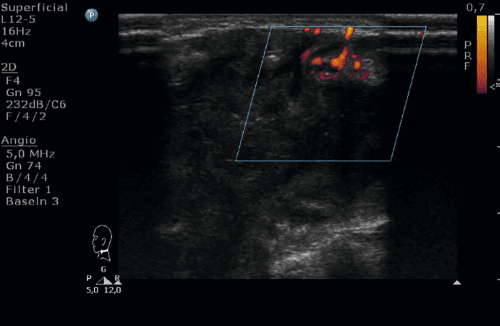

Chłopiec niespełna 16-letni zgłosił się do izby przyjęć z powodu bólu i obrzęku szyi po stronie lewej. Dwa tygodnie wcześniej dziecko przebyło infekcję dróg oddechowych z kaszlem, bez gorączki. Dodatkowo od około tygodnia chłopiec skarżył się na poty nocne. Przy przyjęciu stan ogólny dziecka był dobry, w badaniu fizykalnym z odchyleń od normy: obrzęk szyi, bolesność uciskowa po stronie lewej; ruchomość szyi zachowana. Stwierdzono liczne, drobne węzły chłonne szyjne oraz obecne znacznie powiększone węzły limfatyczne nadobojczykowe i podobojczykowe po stronie prawej. W badaniach laboratoryjnych podwyższona wartość OB. W rtg klatki piersiowej uwidoczniono poszerzenie cienia śródpiersia przedniego. W wykonanym badaniu USG na szyi głównie po stronie prawej i nadobojczykowo zobrazowano liczne węzły chłonne o znacznie zmienionej morfologii, hipoechogeniczne lub o mieszanej echogeniczności, ze słabo widoczną wnęką i wzmożonym unaczynieniem. W pomiarach: węzły nadobojczykowe po stronie prawej wielkości 32 x 9 mm, kolejny 22 x 14 mm (z możliwymi cechami rozpadu), kilka węzłów do 13 mm widocznych było częściowo zamostkowo (najprawdopodobniej w śródpiersiu); po stronie lewej nadobojczykowo obecne były liczne, drobne, hipoechogeniczne węzły chłonne. Unaczynienie węzłów limfatycznych było chaotyczne, zobrazowano naczynia wnikające z obwodu. Dodatkowo uwidoczniono zakrzepicę żyły szyjnej wewnętrznej prawej. Zdecydowano o chirurgicznym usunięciu jednego z węzłów chłonnych. Istotny jest fakt, że do badań histopatologicznych u dzieci pobiera się cały węzeł chłonny. Nie wykonuje się biopsji cienkoigłowej z uwagi na znaczny odsetek niediagnostycznych wyników. Na podstawie badania hist-pat rozpoznano chłoniaka Hodgina i rozpoczęto leczenie onkologiczne.

Chłoniaki ziarnicze i nieziarnicze stanowią około 50–60% zmian złośliwych szyi u dzieci. Umiejscowienie na szyi jest częstsze w przypadku ziarnicy złośliwej niż chłoniaka nieziarniczego. Inne zmiany złośliwe tej okolicy to zwojak zarodkowy, mięsaki (fibrosarcoma, neurofibrosarcoma) oraz histiocytoza z komórek Langerhansa. W toku postępowania diagnostycznego pamiętać należy również o potencjalnie złośliwych zmianach ogniskowych tarczycy, przytarczyc oraz ślinianek. Ważną kwestią jest różnicowanie na podstawie badania ultrasonograficznego chłoniaków z węzłami chłonnymi metastatycznymi. Przerzuty do węzłów u dzieci najczęściej występują w przebiegu mięsaka prążkowanokomórkowego, rzadziej w raku tarczycy i zwojaku zarodkowym. Samo kryterium wielkości węzłów chłonnych rozrostowych uważane jest za niewystarczające. Dopiero seria pomiarów tego samego węzła chłonnego w określonych odstępach czasowych wnosi informacje na temat jego potencjalnie złośliwego charakteru lub odpowiedzi na terapię. Węzły chłonne rozrostowe mają nieprawidłowy okrągły kształt, ponieważ niekontrolowane namnażanie się komórek prowadzi do zmiany ich architektury. Stosunek szerokości do długości węzła limfatycznego budzącego niepokój onkologiczny wynosi powyżej 0,5. Węzły chłonne potencjalnie onkologiczne cechuje znaczne zwężenie, a w dalszej konsekwencji nieobecność wnęki i ekscentryczne poszerzenie kory. Jednak we wczesnej fazie zajęcia węzłów chłonnych przez komórki nowotworowe obserwować możemy prawidłowy obraz wnęki. Węzły w przebiegu chłoniaków zazwyczaj są w całości hipoechogeniczne (mogą przypominać torbiele); w odróżnieniu od węzłów typu przerzutowego, które częściej mają bardziej złożoną strukturę (związane to jest z zachodzącymi w nich zmianami wstecznymi). Węzły chłonne przerzutowe w przebiegu raka brodawkowatego tarczycy są hiperechogeniczne. Zarówno w przypadku chłoniaków, jak i węzłów przerzutowych charakterystyczne jest przerwanie ciągłości torebki węzła chłonnego i naciekanie sąsiednich węzłów chłonnych lub okolicznych tkanek (czyli tworzenie tzw. pakietów). Badając węzły onkologiczne uwidocznić możemy wewnątrz nich fragmenty nekrozy wyrażające się w ultrasonografii jako silnie hipoechogeniczne rejony. Sporadycznie w węzłach nowotworowych występuje martwica koaugacyjna, która odpowiada obszarom hiperechogenicznym. W przypadku chłoniaków rzadziej niż w węzłach przerzutowych dochodzi do nekrozy, wyjątkiem są sytuacje, gdy choroba jest zaawansowana oraz w chłoniakach po leczeniu chemio- i radioterapią. Elementem badania różnicowego węzłów chłonnych rozrostowych jest ocena zwapnień. Ogniska mikrokalcyfikacji charakterystyczne są więc przede wszystkich dla węzłów metastatycznych. Zwapnienia szczególnie często widoczne są w przerzutach raka brodawkowatego tarczycy. Są one zlokalizowane obwodowo i dają cień akustyczny. W przypadku raka rdzeniastego również można uwidocznić pojedyncze mikrozwapnienia, jednak ich występowanie jest dużo rzadsze. Opcje dopplerowskie używane są rutynowo w obrazowaniu węzłów chłonnych nowotworowych i ułatwiają diagnostykę różnicową. W węzłach o potencjalnie onkologicznym charakterze obserwuje się nieprawidłowy mieszany lub obwodowy typ unaczynienia. Zaburzona architektura naczyń jest późnym objawem nowotworzenia, dlatego analizując jedynie wzorzec ukrwienia, nie uda nam się wykluczyć choroby rozrostowej w jej wczesnej fazie. Chłoniaki cechują się głównie unaczynieniem mieszanym, tzn. odwnękowym i obwodowym (w przypadku chłoniaków ogniska martwicy występują rzadko i możliwe jest zachowanie odwnękowego ukrwienia). Węzły chłonne przerzutowe częściej mają unaczynienie wyłącznie obwodowe.Obrazując węzły chłonne nowotworowe, korzystamy z oceny dopplerowskiego widma przepływu. Węzły onkologiczne charakteryzuje wysokooporowe spektrum przepływu (RI > 0,7), które jest zauważalnie wyższe w przerzutach niż w chłoniakach.